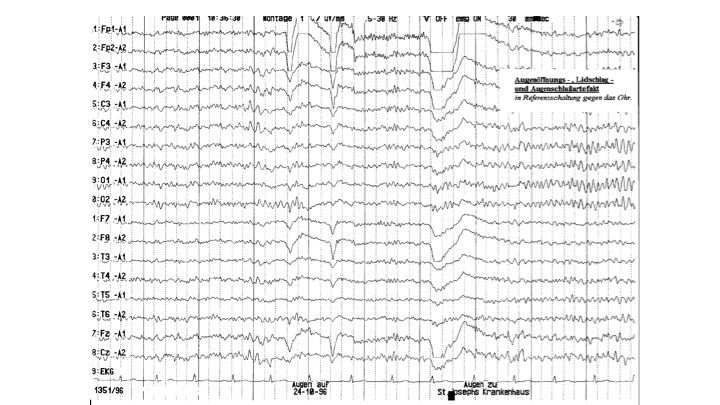

Artefakte im EEG | 6.65 zurück | weiter